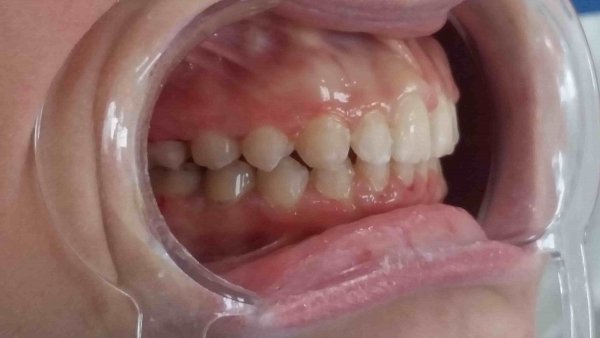

Пациентка 16 лет. Жалобы на неправильное положение зубов, нарушение прикуса.

Ортодонтического лечение проводилось на

Диагноз: Мезиальная окклюзия, тенденция к вертикальной резцовой дизокклюзии, скучное положение зубов.

Фактический срок лечения 25 месяцев